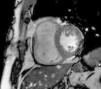

MRI revealed a dilated right ventricle with marked hypokinesia/akinesia of the free wall and EF of 21%. No late enhancement was seen in the myocardium after injection of paramagnetic contrast (Figure 2).

On the basis of these findings, the patient was judged to meet two major and one minor criteria for a definitive diagnosis of arrhythmogenic right ventricular dysplasia (ARVD) according to the 2010 Task Force1 (by MRI: regional RV akinesia or dyskinesia or dyssynchronous RV contraction and RV ejection fraction ≤40%; on ECG: inverted T waves in right precordial leads [V1-V3]; and >500 ventricular extrasystoles per 24 hours by Holter) (Figure 3).